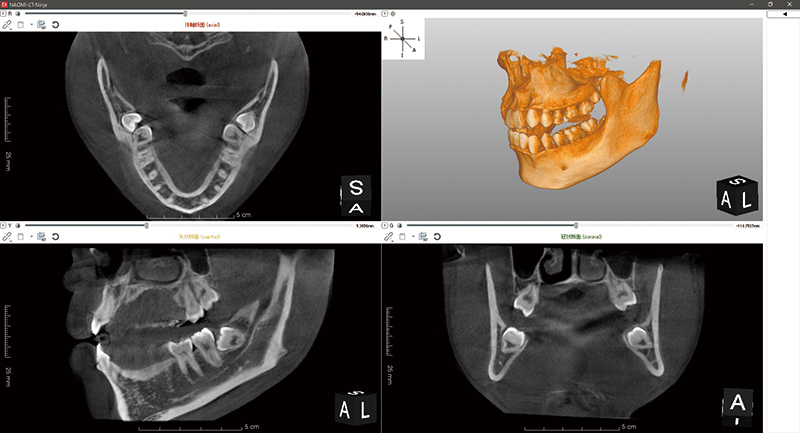

CTとは

CTとはコンピューター断層撮影(Computed Tomography)の略称です。

解析したい部位を細かく輪切りにし、それぞれの断面の画像を撮影する技術です。

歯科用CTでは、歯が失われた部分の骨の幅や深さや骨質、下顎管や上顎洞までの距離を正確に測定することができます。

今までのDental X線やパノラマX線では2次元の情報しか得ることができなかったのが、歯科用CTで撮影することにより3次元の情報を得られるため、より正確な診断が可能になります。

当医院ではインプラントの他、親知らずの抜歯や根管治療、歯周病の治療などに用いています。

インプラント治療においては下顎管や上顎洞の位置関係、骨の幅や深さ、骨質等をきちんと把握することにより、手術時のリスクをを軽減させることができます。

またインプラントの埋め込み位置や挿入深さの決定や患者様への説明にも必要となります。